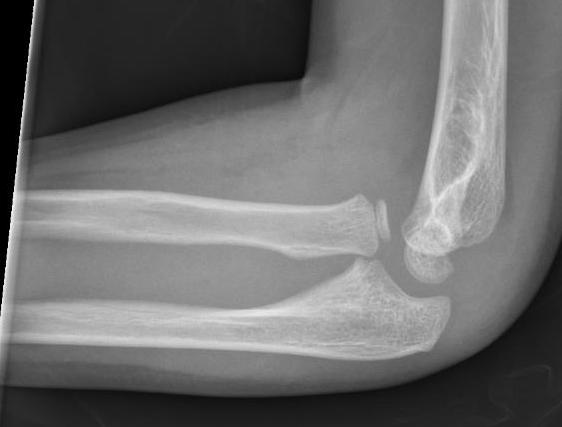

Case 1. Missed Monteggia, injury 6 months ago